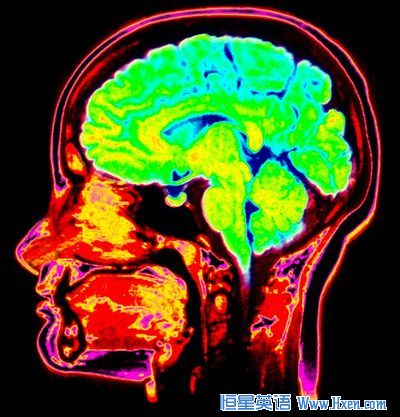

The scientists monitored the dreamers with both magnetic resonance imaging and near-infrared spectroscopy to see patterns of heat in their subject's heads, which gives a picture of brain activity.